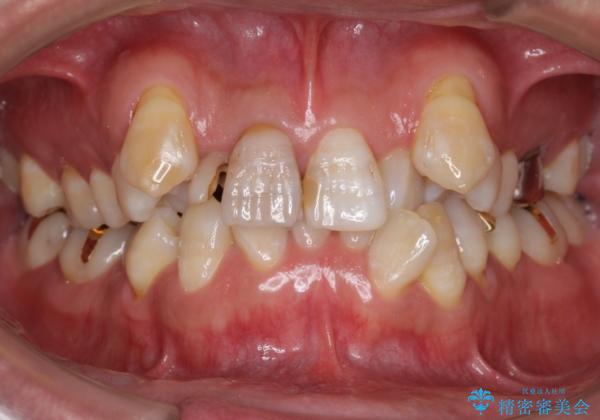

- 神経が死んでいる前歯2本(右上21)をセラミッククラウンでかぶせたいとご希望され、来院された患者様です。

歯並びにより、そのままだときれいに被せ物をいれられない状態でした。

重度の叢生(歯並びのがたがた)のため、

患者様の「できるだけ短期間で治療を終わらせたい、セラミックが入れられたら良いので大がかりなことはしたくない」とのご要望により、3Dシミュレーションを何度も行い患者様とのコンサルを重ね、上顎左右犬歯と左下2を抜歯して②のプランである補綴前矯正(インビザライン)を行うことにしました。

仕上がりに限界はありましたが、比較的短期間で歯並びが整いセラミック治療を行うことができ、患者様に「治療して良かった」とご満足頂けました。

左上1の歯の表面にもともと凹凸とグラデーションがあり、気になるようならセラミックでかぶせるのも一つだと提案しましたがご希望されなかったため、その表面性状を再現して右上1のセラミッククラウンを作製しています。